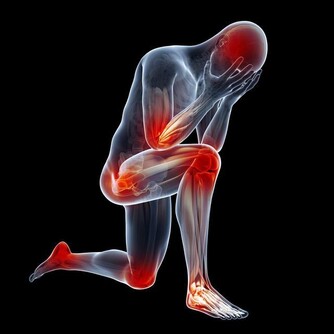

俗話說“十人九腰痛”,腰疼又稱“腰脊痛”。

是因外感、內傷、或挫閃導致腰部氣血運行不暢,或失於濡養,引起腰脊或脊旁部位疼痛為主要症狀的一類疾病。

腰疼是日常生活中非常常見的一種病症,引起腰痛病的原因很多,約有數十種,

比如我們常見的腰間盤突出、腰肌勞損,那麼怎樣測試腰痛屬於哪種類型呢?

1、腰肌勞損---能摸到、有壓痛

腰肌和腰背筋膜疼痛,位置相對比較淺,

如果感覺腰疼,而且能摸到,按壓時有疼痛感,往往可能就是腰背筋膜炎(即腰肌勞損)。

2、腰椎間盤問題---位置很深、活動受限

當腰椎間盤出現問題,其疼痛位置在身體後中心比較深的地方。感覺很疼,甚至活動受到限制,彎不了腰。

但觸摸腰和後背時,並沒有很疼的壓痛點。

這往往是腰椎間盤引起的牽扯痛,或小關節功能紊亂引起的疼痛,確診需要藉助CT或核磁共振。

3、神經受累——腰疼並伴隨下肢放射痛

這是腰椎間盤突出症較為常見的疾患之一,主要是因為腰椎間盤各部分(髓核、纖維環及軟骨板),

尤其是髓核,有不同程度的退行性改變後,在外力因素的作用下,椎間盤的纖維環破裂,

髓核組織從破裂之處突出(或脫出)於後方或椎管內,導致相鄰脊神經根遭受刺激或壓迫,

從而產生腰部疼痛,一側下肢或雙下肢麻木、疼痛等一系列臨床症狀。

4、需排除腫瘤可能——待著不動也疼

出現不明原因的腰疼,又找不到特殊的壓痛點,夜間睡著時也疼得厲害,

處於舒適、放鬆的休息狀態時仍然很疼,必須及時到醫院排除是否為腫瘤,以免延誤治療。